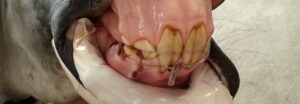

Het oudere paardEOTRH | aandoening aan voornamelijk de snijtanden van een paard

Equine Odontoclastic Tooth Resorption and Hypercementosis (EOTRH) komt voornamelijk voor aan de snijtanden van oudere,…